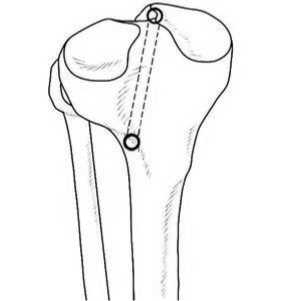

По классической методике транстибиальной фиксации корня медиального мениска канал для проведения нитей формируют в медиальном мыщелке большеберцовой кости, что, по нашему мнению, вследствие дальнейшего натяжения мениска вниз и вперед, зачастую приводит к избыточному «загибанию» его заднего рога, придавая мениску неестественную форму. По этой причине в своей практике канал к точке инсерции корня мениска мы формировали через наружный мыщелок большеберцовой кости, предварительно выполнив к нему передне-наружный послойный доступ протяженностью до 4 см. Благодаря такому расположению канала последующее натяжение мениска происходило кнаружи, вниз и кпереди, что позиционировало его задний рог более анатомично (рис. 3).

Рисунок 3. Схема формирования транстибиального канала через наружный мыщелок большеберцовой кости.

Для формирования канала использовали специальный направитель фирмы производителя Arthrex (рис.4), а также ретроградное сверло FlipCutter (рис.5), которое благодаря своей конструкции позволяло увеличить диаметр концевой части непосредственно в полости сустава и путем обратного рассверливания на 3–4 мм освежать зону инсерции корня для лучшего сращения и сформировать ложе для мениска.